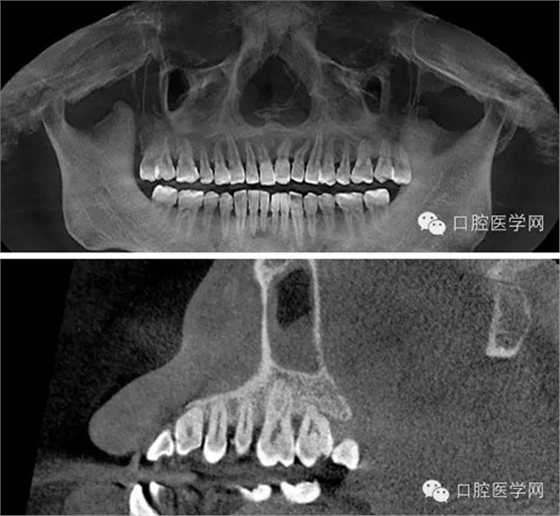

CBCT截圖:26根尖可見低密度透射暗影: